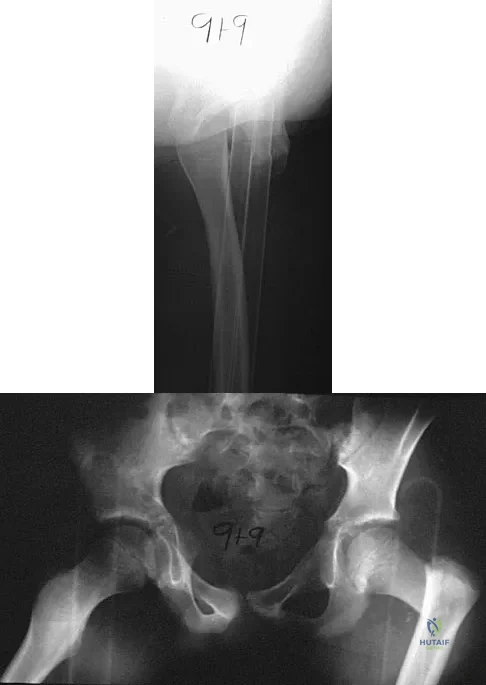

A 51-year-old male truck driver has had progressive left hip pain for more than 2 years, and he reports that the pain has become severe in the past 9 months. He is now unable to work because of the pain. Examination reveals that range of motion of the hip is limited to 95 degrees of flexion, 0 degrees of internal rotation, and 20 degrees of external rotation. The plain radiograph, MRI scan, and intraoperative gross photographs are shown in Figures 9a through 9d. Management should consist of

A 9-year-old child has right groin pain after falling from a tree. Examination reveals that the right leg is held in external rotation, and there is significant pain with attempts at passive range of motion. Radiographs are shown in Figures 43a and 43b. Management should consist of

A 22-year-old man has mild hip pain bilaterally and multiple skeletal lesions. Based on the pelvic radiograph shown in Figure 30, what is the inheritance pattern for his disorder?